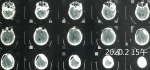

思考:慢性硬膜下血腫術(shù)后再出血的病因? 關(guān)鍵疾病:慢性硬膜下血腫(雙側(cè)額顳頂枕部) 現(xiàn)病史【一般資料】 男性,58歲,農(nóng)民 【主訴】 頭部外傷2個月,頭痛20余天。 【現(xiàn)病史】患者于2個月前駕車撞到路邊,致頭部受傷,未治療。20余天前患者感頭痛,呈陣發(fā)性脹痛,無頭暈,無惡心、嘔吐,無肢體抽搐,無大小便失禁,院外未做診治,急來我院就診,行顱腦CT檢查示“雙側(cè)額顳部慢性硬膜下血腫”,口服藥物治療。服藥后頭痛無明顯緩解,為求診治,再次來診,門診以“慢性硬膜下血腫”收住我科?;颊咦园l(fā)病以來,神志清,精神可,飲食、睡眠可,大小便正常,體重?zé)o明顯變化。 【既往史】既往體健。否認(rèn)“高血壓、心臟...

祝***磊 | 主治醫(yī)師 外科 神經(jīng)外科 瀏覽:4126